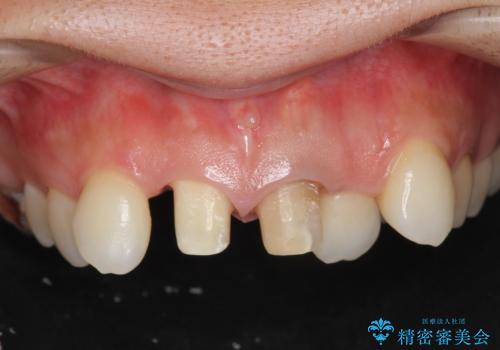

著しいがたつきによる清掃困難 歯牙抜去とセラミック治療

- 前歯の変色の改善を希望され来院されました。

X線写真より、充填剤の突き出た状態の根管治療の再治療を行い、セラミック治療を計画すると同時に、

歯ブラシがしづらく虫歯の原因となっている歯の位置の悪い右上側切歯の抜去を行います。

清掃を難しくしている歯を抜去することで虫歯の再発を防ぐような治療方針としました。